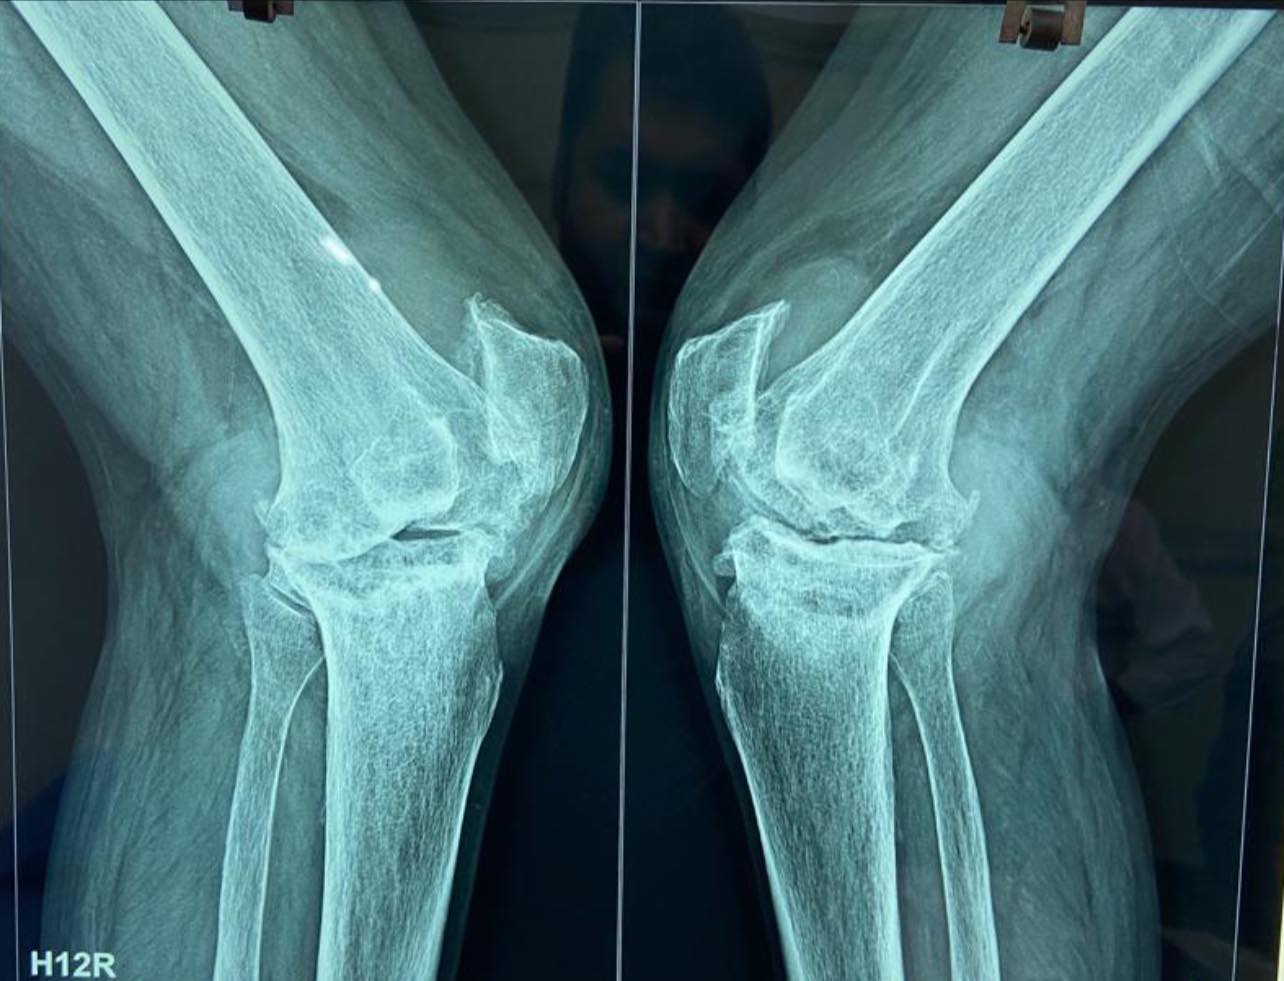

48-year-old male with windswept deformity of knees due to rheumatoid arthritis, both femoral lateral condyles are hypoplastic. Left tibia has a medial bone defect of 20 mm. Treated with long stem prostheses for tkr (total knee replacement) with semi-constrained liners. For the left knee bone defect, bone grafting was done with cc screw fixation.